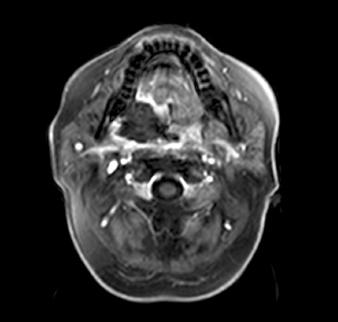

Metastasis of cutaneous melanoma to the oral cavity is a rare condition. Male patient with cutaneous melanoma metastasis to right tonsil 2 years after radical skin lesion resection was treated with surgery: tonsillectomy and later resection of soft palate were performed. Two years later the patient was diagnosed with progressive disease to right tonsil and soft palate. Rapid inoperable relapse was detected six months later. The patient underwent two procedures of palliative cryoablation of the metastasis. Postoperative course was uneventful. Patient died 7 months later due to progression of the disease. Cryoablation alone or together with surgery may be a relatively safe option for treatment of inoperable disease of head and neck tumours.

皮肤黑色素瘤转移至口腔是一种罕见的情况。一名男性患者在皮肤病变根治性切除术后2年出现皮肤黑色素瘤转移至右侧扁桃体,接受了手术治疗:进行了扁桃体切除术,随后切除了软腭。两年后,患者被诊断为右侧扁桃体和软腭疾病进展。六个月后检测到快速进展且无法手术切除的复发。患者接受了两次转移性病变的姑息性冷冻消融治疗。术后过程顺利。患者7个月后因疾病进展死亡。单独冷冻消融或与手术联合使用可能是治疗头颈部肿瘤无法手术切除疾病的相对安全的选择。